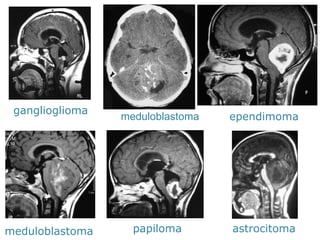

ganglioglioma

meduloblastoma

ependimoma

papiloma

astrocitoma

ganglioglioma meduloblastoma ependimoma meduloblastoma papiloma astrocitoma